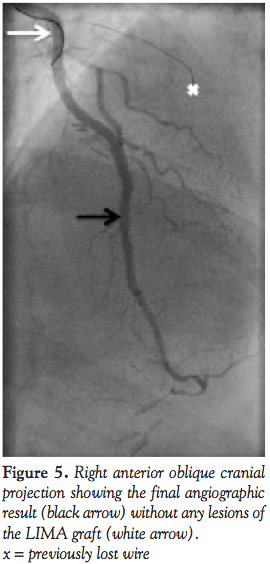

At this moment, the only remaining option to improve the back-up support was to use a dedicated guide-extension microcatheter. The Guideliner Microcatheter (Vascular Solutions), was easily advanced (ie, telescoping technique) through the LIMA and directly placed in the previously implanted stent at the angulation site (Figure 4). With this maneuver, the back-up support of the entire system improved dramatically, and allowed without any further friction or resistance the implantation of the Xience stent, finally successfully sealing the LAD dissection (Figure 5). Final angiographic assessment once the wires and the Guideliner were retrieved showed a patent LIMA graft without any sign of spasm or iatrogenic complications.